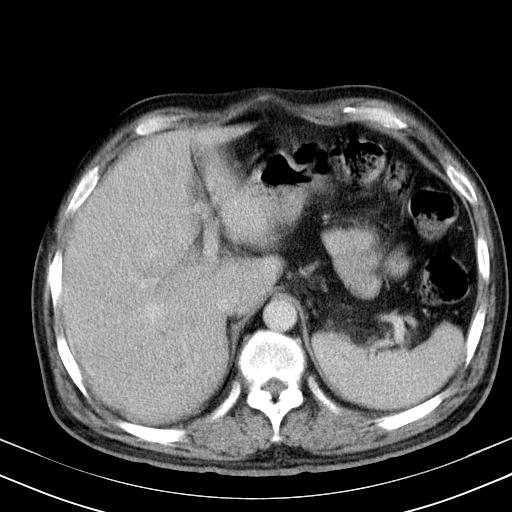

先行ct平扫,纵膈内多发软组织影,ct值约为36hu,以下为增强扫描和腹部平扫。

经典?纵膈多发肿大淋巴结。腹膜后未见异常。

大家看看肝脏右叶片状低密度影是什么改变啊?

淋巴瘤?肝脏请增强后说啊

多发肿大淋巴结影,肝内改变需结合强化观察

多发肿大淋巴结影,肝内改变需结合强化观察。